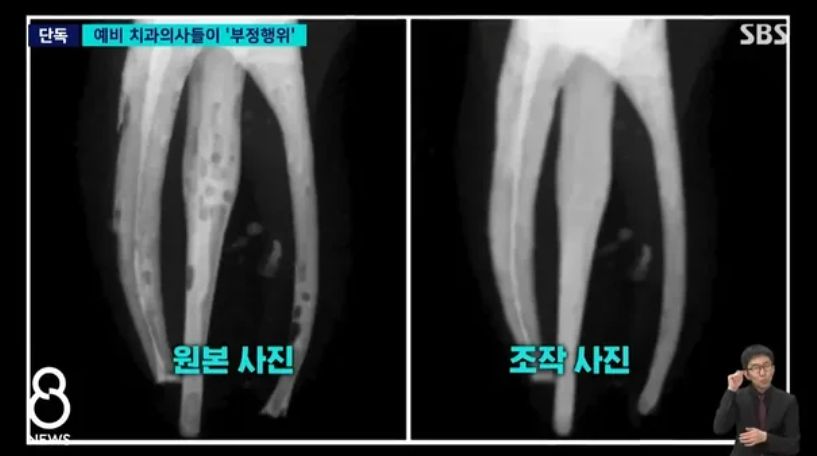

학생들이 조작한 사진은 신경치료를 거쳐 깨끗해진 치아 뿌리를 담은 엑스레이 사진이다. 그러나 이는 포토샵으로 조작된 것으로, 실제 사진 속 치아 뿌리는 충전재를 꼼꼼히 채워 넣지 않아 곳곳에 구멍이 뚫린 모습이었다.